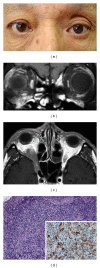

Orbital IgG4-related disease, which can occur in adults of any age, is characterized by IgG4-positive lymphoplasmacytic infiltrations in ocular adnexal tissues. The signs and symptoms include chronic noninflammatory lid swelling and proptosis. Patients often have a history of allergic disease and elevated serum levels of IgG4 and IgE as well as hypergammaglobulinemia. Orbital IgG4-related disease must be differentiated from idiopathic orbital inflammation and ocular adnexal marginal zone B-cell lymphoma to ensure appropriate and effective treatment. Systemic steroid therapy decreases the size of the lesions, but relapse often occurs when systemic steroid therapy is discontinued.